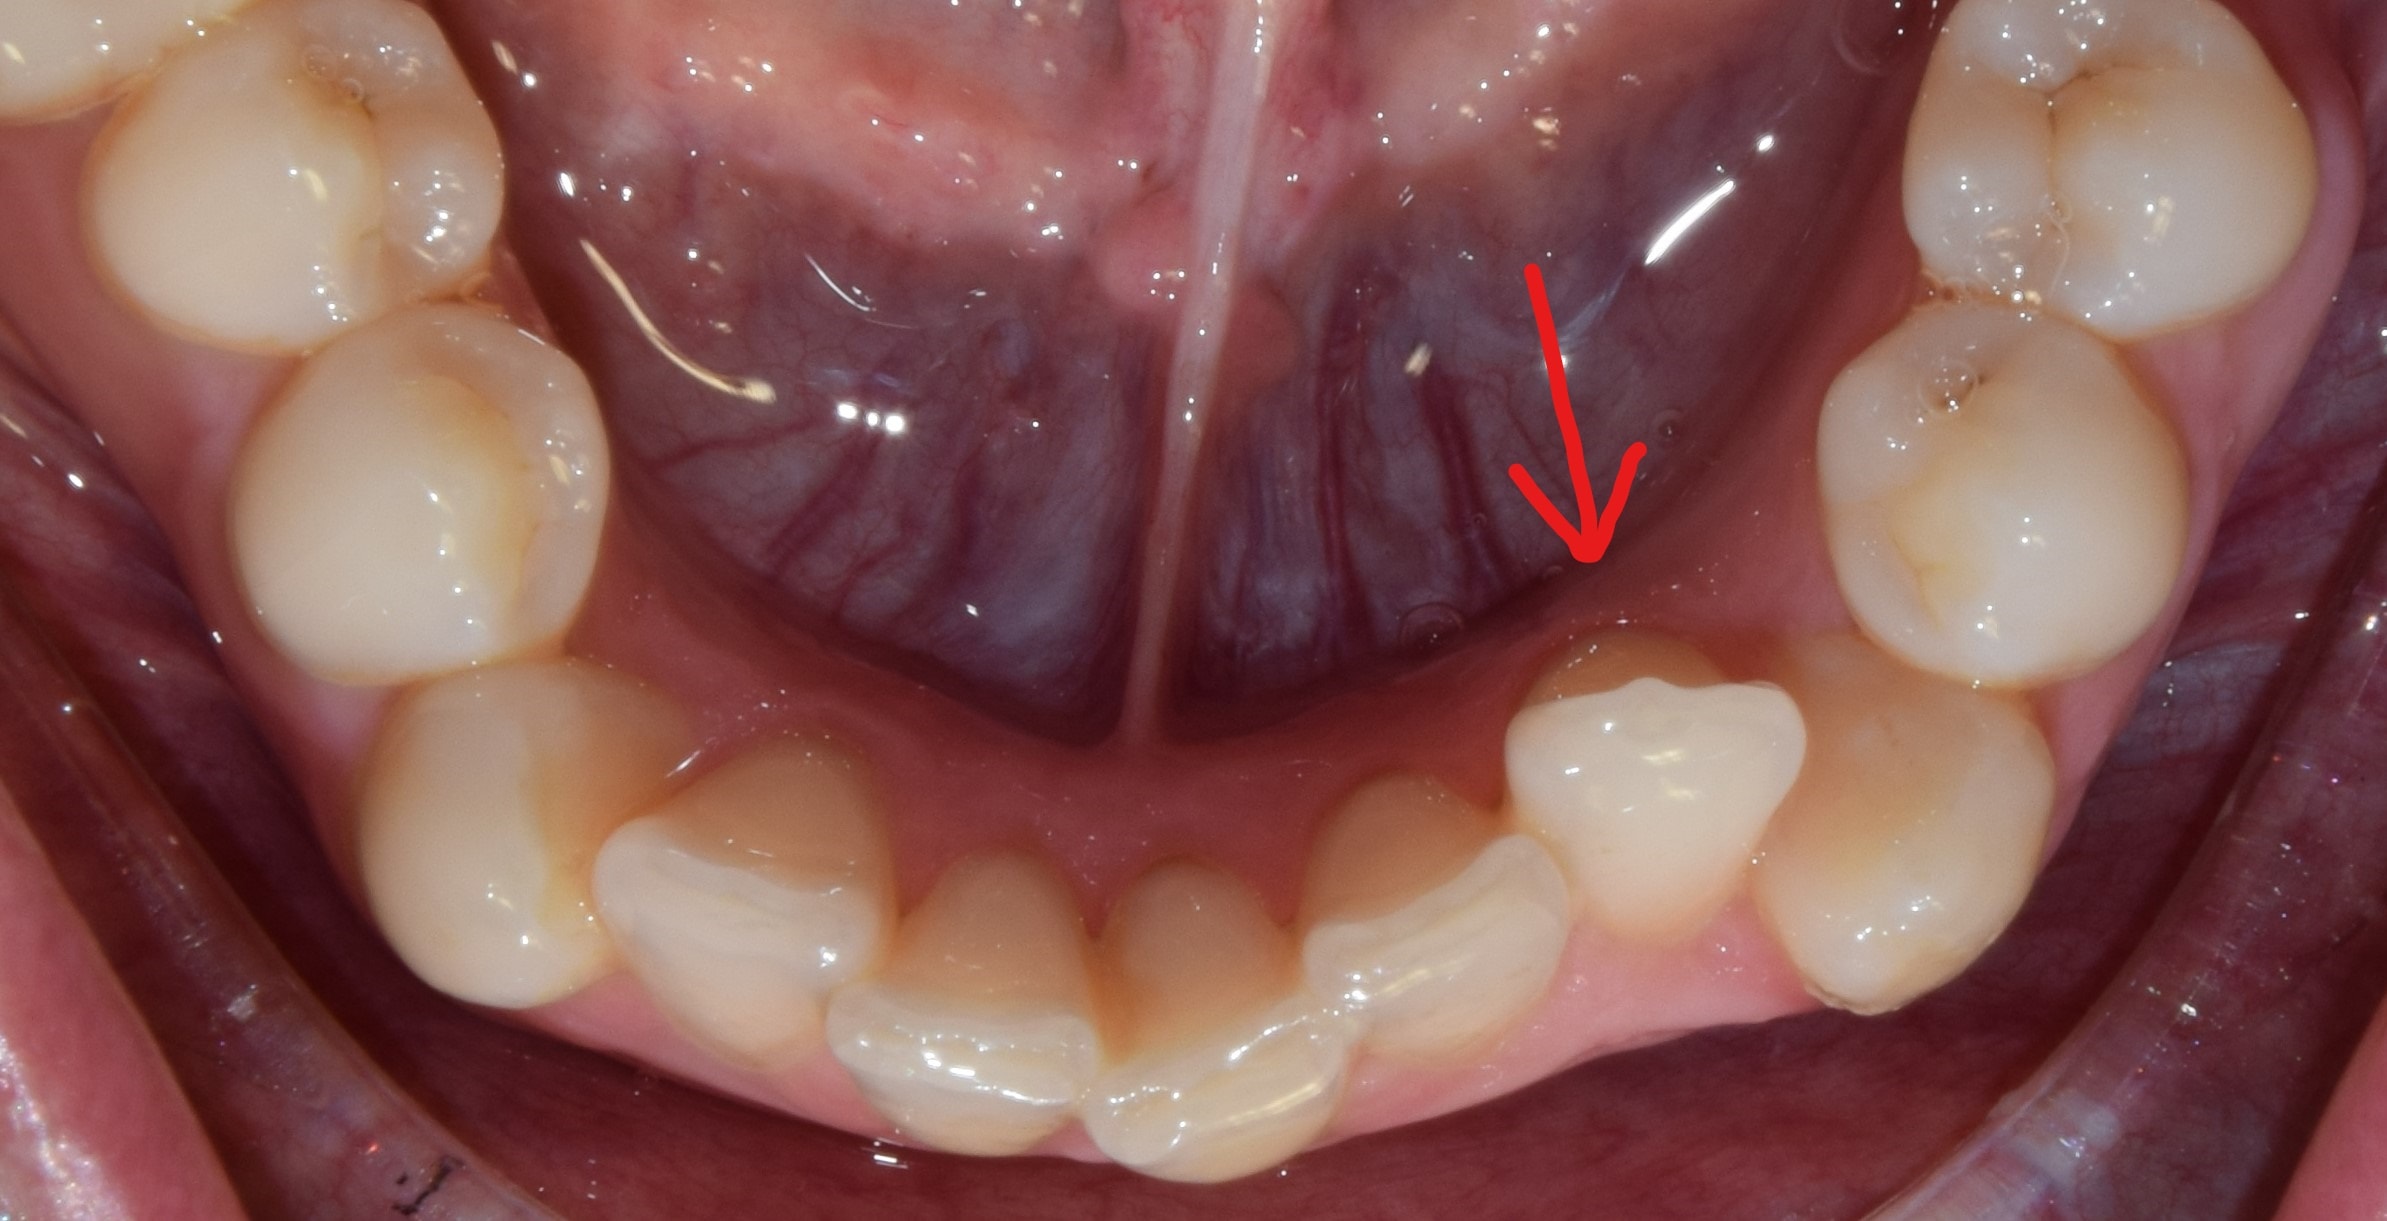

Diasthema medianum

Gyakori fogszabályozási probléma a két felső nagymetsző között jelentkező rés. Ellátását számos faktor befolyásolja. A vegyesfogazatban gyakori, legtöbbször normális jelenség, ami később spontán záródhat, ezért túlságosan korai ellátását semmi sem indokolja. Diasthemat eredményezhet például kifejezett ajakfék, számfeletti fog, kismetsző csírahiány.

Az ajakfék nem más, mint az ajkak mozgását szabályozó, korlátozó nyálkahártya tömörülés, mely az alsó és felső első metszők fölött-között helyezkedik el. A túlságosan kifejezett ajakfék beszédproblémát, ínyvisszahúzódást, vagy akár rést is okozhat a metszőfogak között. A köteges, kifejezett ajakféket egy kis szájsebészeti beavatkozás során korrigálni lehet, legkíméletesebben lézerrel.